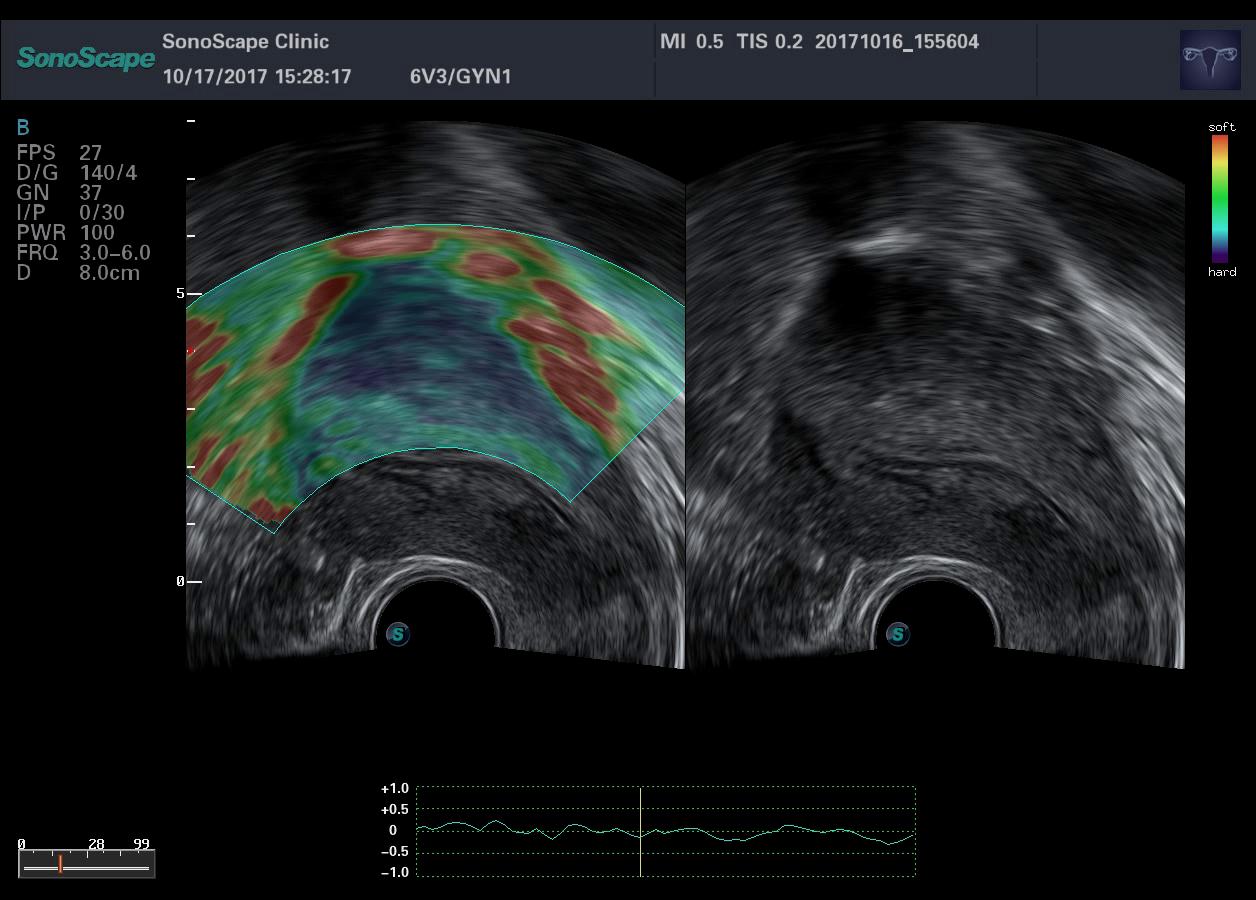

- Режим СоноЭластографии с количественной оценкой